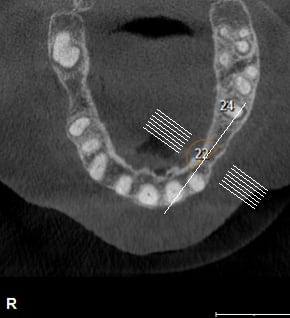

petit cas sympa ancien bridge très mobile....plutôt que d'extraire 25, j'ai déposé la couronne, retraité la dent stabilisation pendant deux mois puis séance d'ostéotension et ce jour pose de deux axioms PX 34120 après expansion...